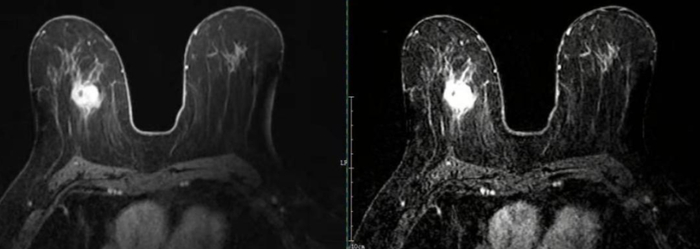

乳腺疾病检查是否可以做核磁共振

可以做的,目前的研究表明,核磁共振检查乳腺疾病的灵敏性、特异性和准确性都很高,均达到90%以上,可以检出B超和钼靶无法检出的肿瘤,尤其是致密性乳腺或者靠近腋窝的肿瘤,多中心或者多灶性的病变,需要进行乳腺的核磁共振检查。一般钼靶X线检查对于恶性肿瘤的检出率大概在60-70%左右,但是对钙化灶的检出率相对磁共振可以高出约50%。

不过由于磁共振的价格较高,预约时间较长,还需要注射造影剂,可能导致过敏,因此目前我们不作为筛查疾病的常规手段,而是建议B超或钼靶有怀疑但不能确定恶性疾病的患者、有乳腺癌家族史,或者有乳腺癌高危因素的的女性朋友筛查。